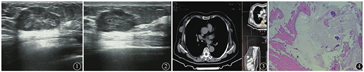

患者女性,76岁。1个月前无意间触及右侧乳腺有1包块来我院就诊。触诊包块约一角钱币大小,表面皮肤正常,无破溃、酒窝征及橘皮样改变,无触痛、乳头溢液。查体:患者无发热、畏寒、乏力、食欲不振。检验结果:肿瘤6项中癌胚抗原升高(6.44 μg/L),甲状腺功能6项中抗甲状腺球蛋白抗体(206.40 kU/L)、抗甲状腺过氧化物抗体(61.82 kU/L)均升高,尿沉渣白细胞(14个/μl)、上皮细胞(89个/μl)亦升高;生化全项中尿酸(480 μmol/L)升高,全血细胞计数、氨基末端-B型利钠肽前体、肌钙蛋白T、肌钙蛋白I、凝血5项未见异常。丙肝、人类免疫缺陷病毒抗体、梅毒、甲型肝炎、乙型肝炎均未见异常。B超检查:右侧乳腺9点位探及大小约3.4 cm×1.3 cm的长椭圆形低回声团,边界较清,可见完整包膜,内回声分布稍欠均,后方回声增强,彩色多普勒血流显像周围及内部未见明显血流信号。右侧腋下未见异常的肿大淋巴结回声。提示:右侧乳腺实性包块,乳腺纤维腺瘤可能。见图1、图2。胸部螺旋CT示右侧乳腺外缘见类圆形软组织影,CT值约28 HU,直径约2.4 cm,结论为右侧乳腺结节,见图3。术中快速冰冻组织病理检查显示:第1次送检,右侧乳腺肿瘤为红色胶样物质,大小2.0 cm×1.8 cm×0.6 cm,其中可见一大小1.2 cm×1.0 cm×0.2 cm的不规整组织一块,冰冻全包;第2次送检:右侧乳腺肿瘤为灰红色破碎软组织,大小1.1 cm×0.7 cm×0.3 cm。镜检显示送检物为少量结缔组织和大量黏液样物,黏液组织中见散在分布的细胞团,呈条索状状排列,部分呈乳头状,细胞形态温和,异型性不大,考虑为黏液性肿瘤,见图4。术后患者恢复良好出院。